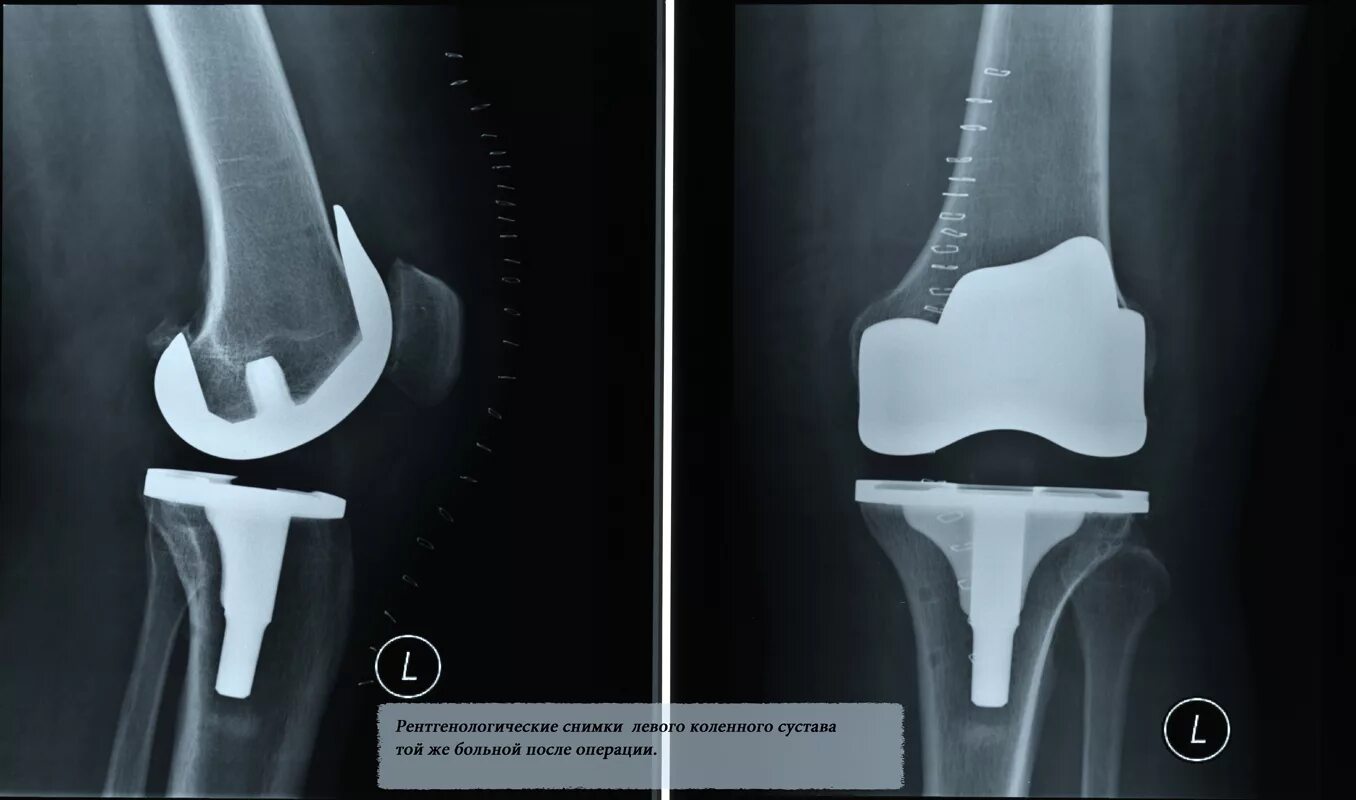

Нестабильность коленного сустава симптомы